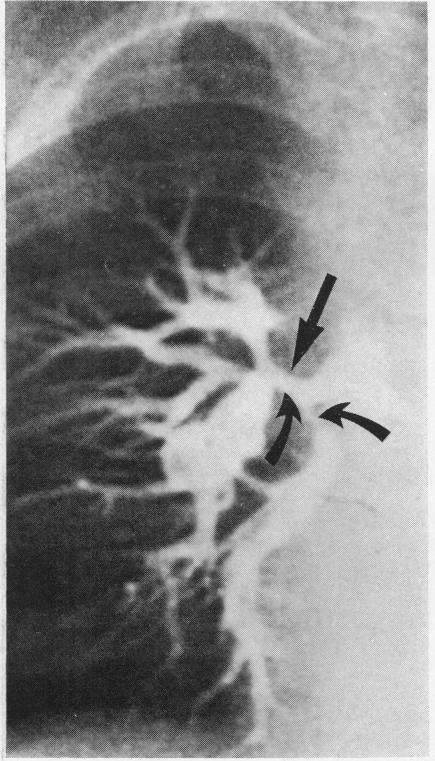

In nine patients with pulmonary atresia, ventricular septal defect, and major aortopulmonary collateral arteries, the effect of a systemic-pulmonary anastomosis on the lung was studied by comparison of pre- and postoperative cine angiograms. Selective injections into the collateral arteries were performed in all patients and the source of blood supply to each bronchopulmonary segment was sought. Central pulmonary arteries were present in six children and absent in three, as confirmed at thoracotomy. After insertion of a shunt, central pulmonary arteries increased in size, but the intrapulmonary vessels with which they connected remained abnormally small and were frequently stenosed. In addition, in each case the central pulmonary arteries increased flow to only five to 11 segments of lung. In the absence of central pulmonary arteries, shunting to a hilar or a lobar pulmonary artery increased perfusion to five to nine segments of lung per case. In all these three cases the pulmonary arteries at lobar level showed aneurysmal dilatation proximal to a severe stenosis. Sixty-eight per cent of collateral arteries were stenosed. The findings suggest that in this anomaly, when the central pulmonary arteries are hypoplastic, the intrapulmonary branches are also hypoplastic, emphasising the need for early surgical intervention to increase blood flow while the lung still has growth potential. Further, one collateral artery may connect with at least as many bronchopulmonary segments as does a central pulmonary artery, and the peripheral intrapulmonary arteries with which it connects may appear at least as normal angiographically as do vessels connected to central pulmonary arteries. These observations suggest that segments of lung connected to collaterals alone should, and sometimes can, be connected to central pulmonary arteries, the aim being to produce a unifocal blood supply as a prelude to total correction.

在9例患有肺动脉闭锁、室间隔缺损和主要体肺侧支动脉的患者中,通过比较术前和术后的电影血管造影来研究体肺分流术对肺的影响。对所有患者的侧支动脉进行了选择性注射,并寻找每个支气管肺段的血供来源。开胸手术证实,6名儿童存在中央肺动脉,3名儿童不存在中央肺动脉。插入分流管后,中央肺动脉尺寸增大,但其相连的肺内血管仍异常细小且常出现狭窄。此外,在每种情况下,中央肺动脉仅使5至11个肺段的血流增加。在没有中央肺动脉的情况下,向肺门或叶肺动脉分流使每例患者5至9个肺段的灌注增加。在所有这3例病例中,叶水平的肺动脉在严重狭窄近端呈瘤样扩张。68%的侧支动脉存在狭窄。这些发现表明,在这种畸形中,当中央肺动脉发育不全时,肺内分支也发育不全,这强调了在肺仍有生长潜力时尽早进行手术干预以增加血流量的必要性。此外,一条侧支动脉可能与至少和中央肺动脉一样多的支气管肺段相连,并且其相连的外周肺内动脉在血管造影上可能至少和与中央肺动脉相连的血管一样正常。这些观察结果表明,仅与侧支相连的肺段应该并且有时能够与中央肺动脉相连,目的是形成单一血供作为完全矫正的前奏。